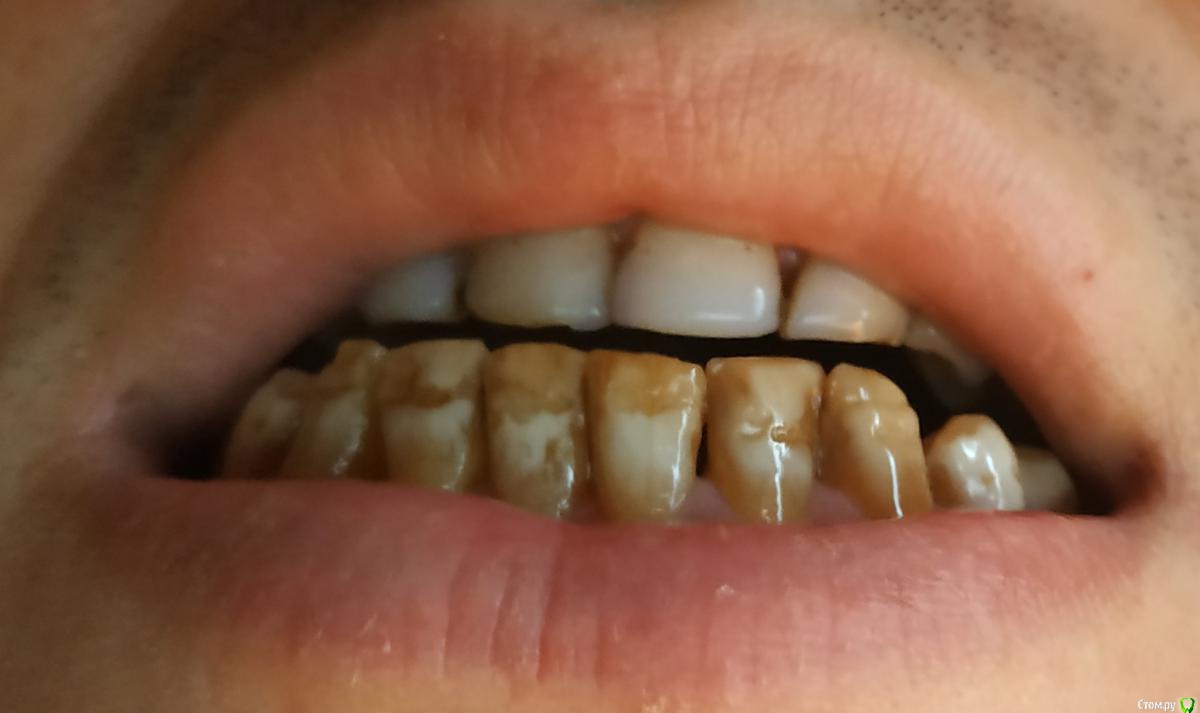

stoch Опубликовано 27 января, 2019 Поделиться Опубликовано 27 января, 2019 (изменено) Доброго времени, уважаемые специалисты.Буду признателен за высказанное мнение. Описание ситуации:С детства испытываю проблемы с зубами по части эстэтического вида. До переезда в Москву жил в небольшом городе, где у многих до определенного времени были похожие проблемы с зубами (возможно причина в переизбытке фтора). Примерно 8 лет назад в том же небольшом городе на 8-ми верхним зубах сделал композитное отбеливание. Периодически для части зубов эту процедуру приходилось повторять при различных повреждениях. На текущий момент помимо неудовлетворенности эстетическим видов зубов, после еды, иногда испытываю дискомфорт в зубах. Все зубы живые.Насколько я понимаю, то использование виниров в моём случае не поможет, а МК коронки имеют массу недостатков и в дальнейшем не очень бы хотелось тратить своё время на решение проблем с ними. Посещая стоматологические клиники мне предлагали сделать для всех зубов коронки из диоксида циркония, предварительно пройдя лечение. Не могу понять и решить, стоит вкладываться в это или есть высокий риск дальнейших проблем с зубами?Также не могу понять ценник: есть коронки, например за 15 тыр., а также за 35 тыр. Как это повлияет, например 1-й вариант прослужит 10 лет, а второй 20? Или там учитываются другие критерии? Каков риск поиска минимального ценника для коронок на основе диоксида циркония?Спасибо. Изменено 27 января, 2019 пользователем stoch Ссылка на комментарий

DmitrySH Опубликовано 27 января, 2019 Поделиться Опубликовано 27 января, 2019 Панорамный снимок вам в любом случае потребуется и ходить с ним на консультации намного информативнее.Сами по себе зубы ( на фото) не представляют какой-то особой сложности для изготовления красивых керамических реставраций 2 Ссылка на комментарий

DmitrySH Опубликовано 30 января, 2019 Поделиться Опубликовано 30 января, 2019 Или есть смысл оставить так как есть? У вас же тут не только неудовлетворительный внешний вид.Присутствует стираемость, пломбы в неудовлетворительном состоянии, местами парадонтальные карманы. зуб 46 разрушается. Меня беспокоит вопрос: приобретя хороший эстетический вид зубов в перспективе не станет хуже для их внутреннего здоровья Если все грамотно сделать, то будет только лучше. И конечно от Вас потребуется качественное поддержание гигиены полости рта. 1 Ссылка на комментарий

stoch Опубликовано 30 января, 2019 Автор Поделиться Опубликовано 30 января, 2019 (изменено) У вас же тут не только неудовлетворительный внешний вид.Присутствует стираемость, пломбы в неудовлетворительном состоянии, местами парадонтальные карманы. зуб 46 разрушается. Если все грамотно сделать, то будет только лучше. И конечно от Вас потребуется качественное поддержание гигиены полости рта. Спасибо, Дмитрий.Даже не знаю почему такая беда с зубами произошла, но уже ничего не поделать и переживать об этом смысла нет. В плане гигиены стараюсь соблюдать базовые правила: если есть возможность, то после приёма пищи чищу, регулярно использую зубную нить. Позвольте задать ещё вопрос. Если депульпировать большую часть зубов, то в итоге чем это грозит? Изменено 30 января, 2019 пользователем stoch Ссылка на комментарий